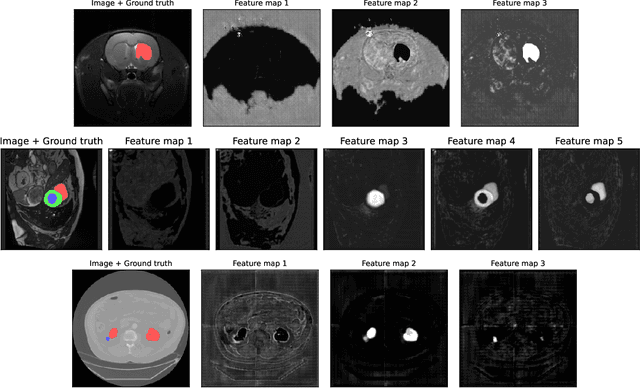

Abstract:We present Sauron, a filter pruning method that eliminates redundant feature maps by discarding the corresponding filters with automatically-adjusted layer-specific thresholds. Furthermore, Sauron minimizes a regularization term that, as we show with various metrics, promotes the formation of feature maps clusters. In contrast to most filter pruning methods, Sauron is single-phase, similarly to typical neural network optimization, requiring fewer hyperparameters and design decisions. Additionally, unlike other cluster-based approaches, our method does not require pre-selecting the number of clusters, which is non-trivial to determine and varies across layers. We evaluated Sauron and three state-of-the-art filter pruning methods on three medical image segmentation tasks. This is an area where filter pruning has received little attention and where it can help building efficient models for medical grade computers that cannot use cloud services due to privacy considerations. Sauron achieved models with higher performance and pruning rate than the competing pruning methods. Additionally, since Sauron removes filters during training, its optimization accelerated over time. Finally, we show that the feature maps of a Sauron-pruned model were highly interpretable. The Sauron code is publicly available at https://github.com/jmlipman/SauronUNet.